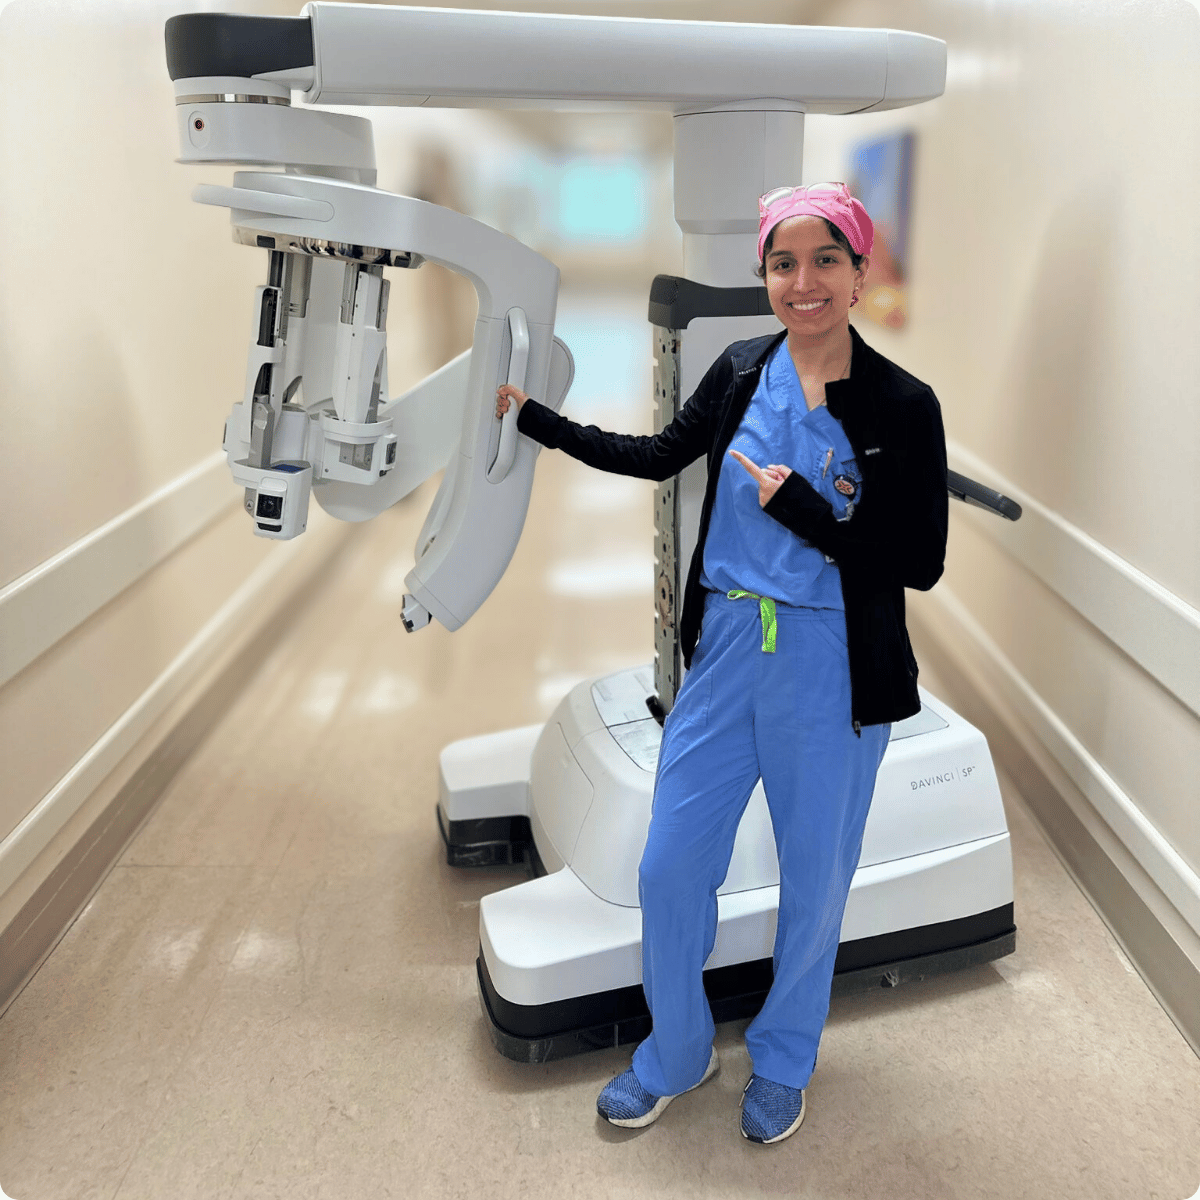

En lo que respecta a la nefrectomía parcial de puerto único para el cáncer de riñón, la Dra. Shirin Razdan es una autoridad reconocida en urología robótica. Con sede en Miami, se ha ganado la reputación de estar a la vanguardia de la cirugía renal mínimamente invasiva, ayudando a los pacientes a lograr excelentes resultados con tiempos de recuperación más cortos. En su último caso práctico quirúrgico, la Dra. Razdan demuestra la nefrectomía parcial de puerto único mediante acceso anterior bajo (AAL), un enfoque altamente refinado que combina precisión, eficiencia y comodidad para el paciente. Este video ofrece una mirada excepcional tras bambalinas sobre cómo las técnicas robóticas de vanguardia están transformando la cirugía del cáncer de riñón.Qué demuestra el video

Dra. Shirin Razdan: Liderando el camino en Miami

Como reconocida cirujana renal robótica en Miami, la Dra. Razdan se compromete a impulsar técnicas mínimamente invasivas que prioricen tanto la precisión quirúrgica como el bienestar del paciente. Su experiencia en cirugía robótica de puerto único la sitúa entre un selecto grupo de cirujanos a nivel nacional que están ayudando a redefinir los estándares en cirugía oncológica urológica. En su consultorio del sur de Florida, la Dra. Razdan utiliza las técnicas quirúrgicas más modernas con un enfoque centrado en el paciente. Cada plan de tratamiento es cuidadosamente personalizado, lo que garantiza que los pacientes no solo reciban atención quirúrgica de primera clase, sino también orientación compasiva durante su proceso de cáncer de riñón.Beneficios para el Paciente